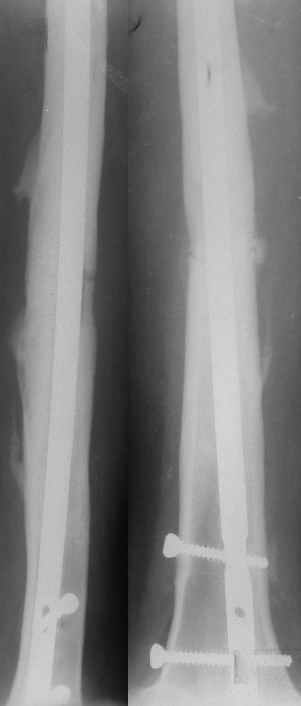

Уважаемые коллеги.Пациентка 18 лет поступила через 6 недель после блокированного остеосинтеза бедра с жалобами на повышение Т до 38гр., незначительной интенсивности боли в Н/3 оперированного бедра, возникающие при движениях (сгибание свыше 90гр.) в коленном суставе. Местно: признаков воспаления, отёка не найдено, пальпация безболезненная. ОАК - N, в моче - капли жира. Картину расценили как проявление жировой эмболии, в течении недели проводилась инфузионная терапия, дезагреганты, постельный режим. Т - N, в моче - жир сохраняется. История болезни этой пациентки началась 5 лет назад с перелома бедра в ДТП, оперирована 2-ы пластиной накостно в одной из больниц нашего города, 2-ы перелом импланта, после последнего раза поступила в нашу клинику, где был выполнен блокированный остеосинтез. Через два года гвоздь удалён (по просьбе больной), Rg-сращение. Через год после удаления рефрактура от незначительной травмы, остеосинтез гвоздём с блок., в раннем послеоперац. периоде жировая эмболия, после купирования амбул. лечение.Прошу советов по дальнейшему лечению. перелом пластины после I опер |  перелом пластины после II опер |  III опер. |  рефрактура через год после удаления штифта |  через мес. после последнего остеосинтеза |